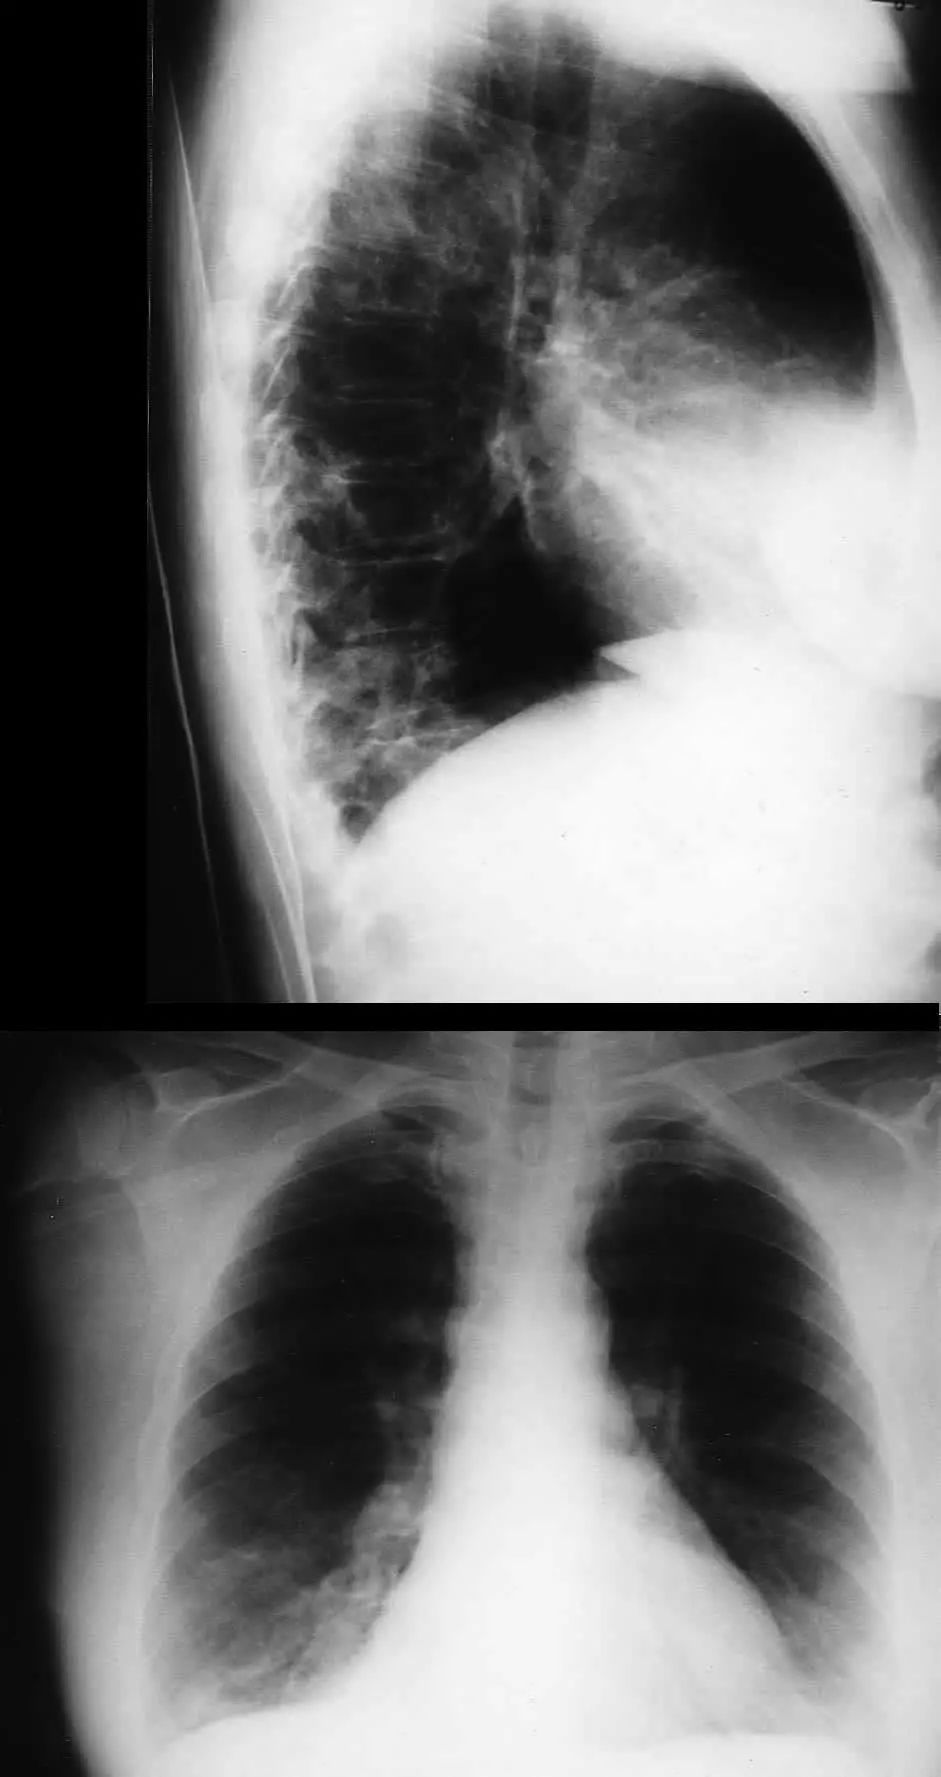

图1.3 细菌性肺炎。早期右肺中叶肺炎的影像学表现。

图1.4 53岁的严重军团菌肺炎患者。胸片显示双肺下叶致密实变。